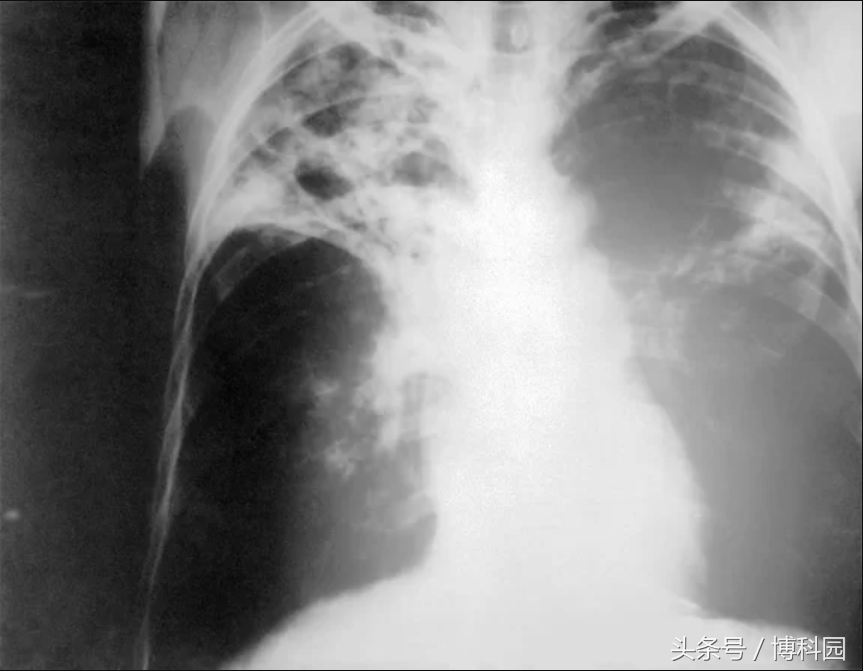

可能致命的“肺结核”是由结核分枝杆菌引起,这种细菌通常会攻击肺部并引起咯血。图中x射线显示了一位患有晚期肺结核的病人胸部。这种细菌并不能使每个人感染肺结核,目前世界上有三分之一的人携带了这种细菌。